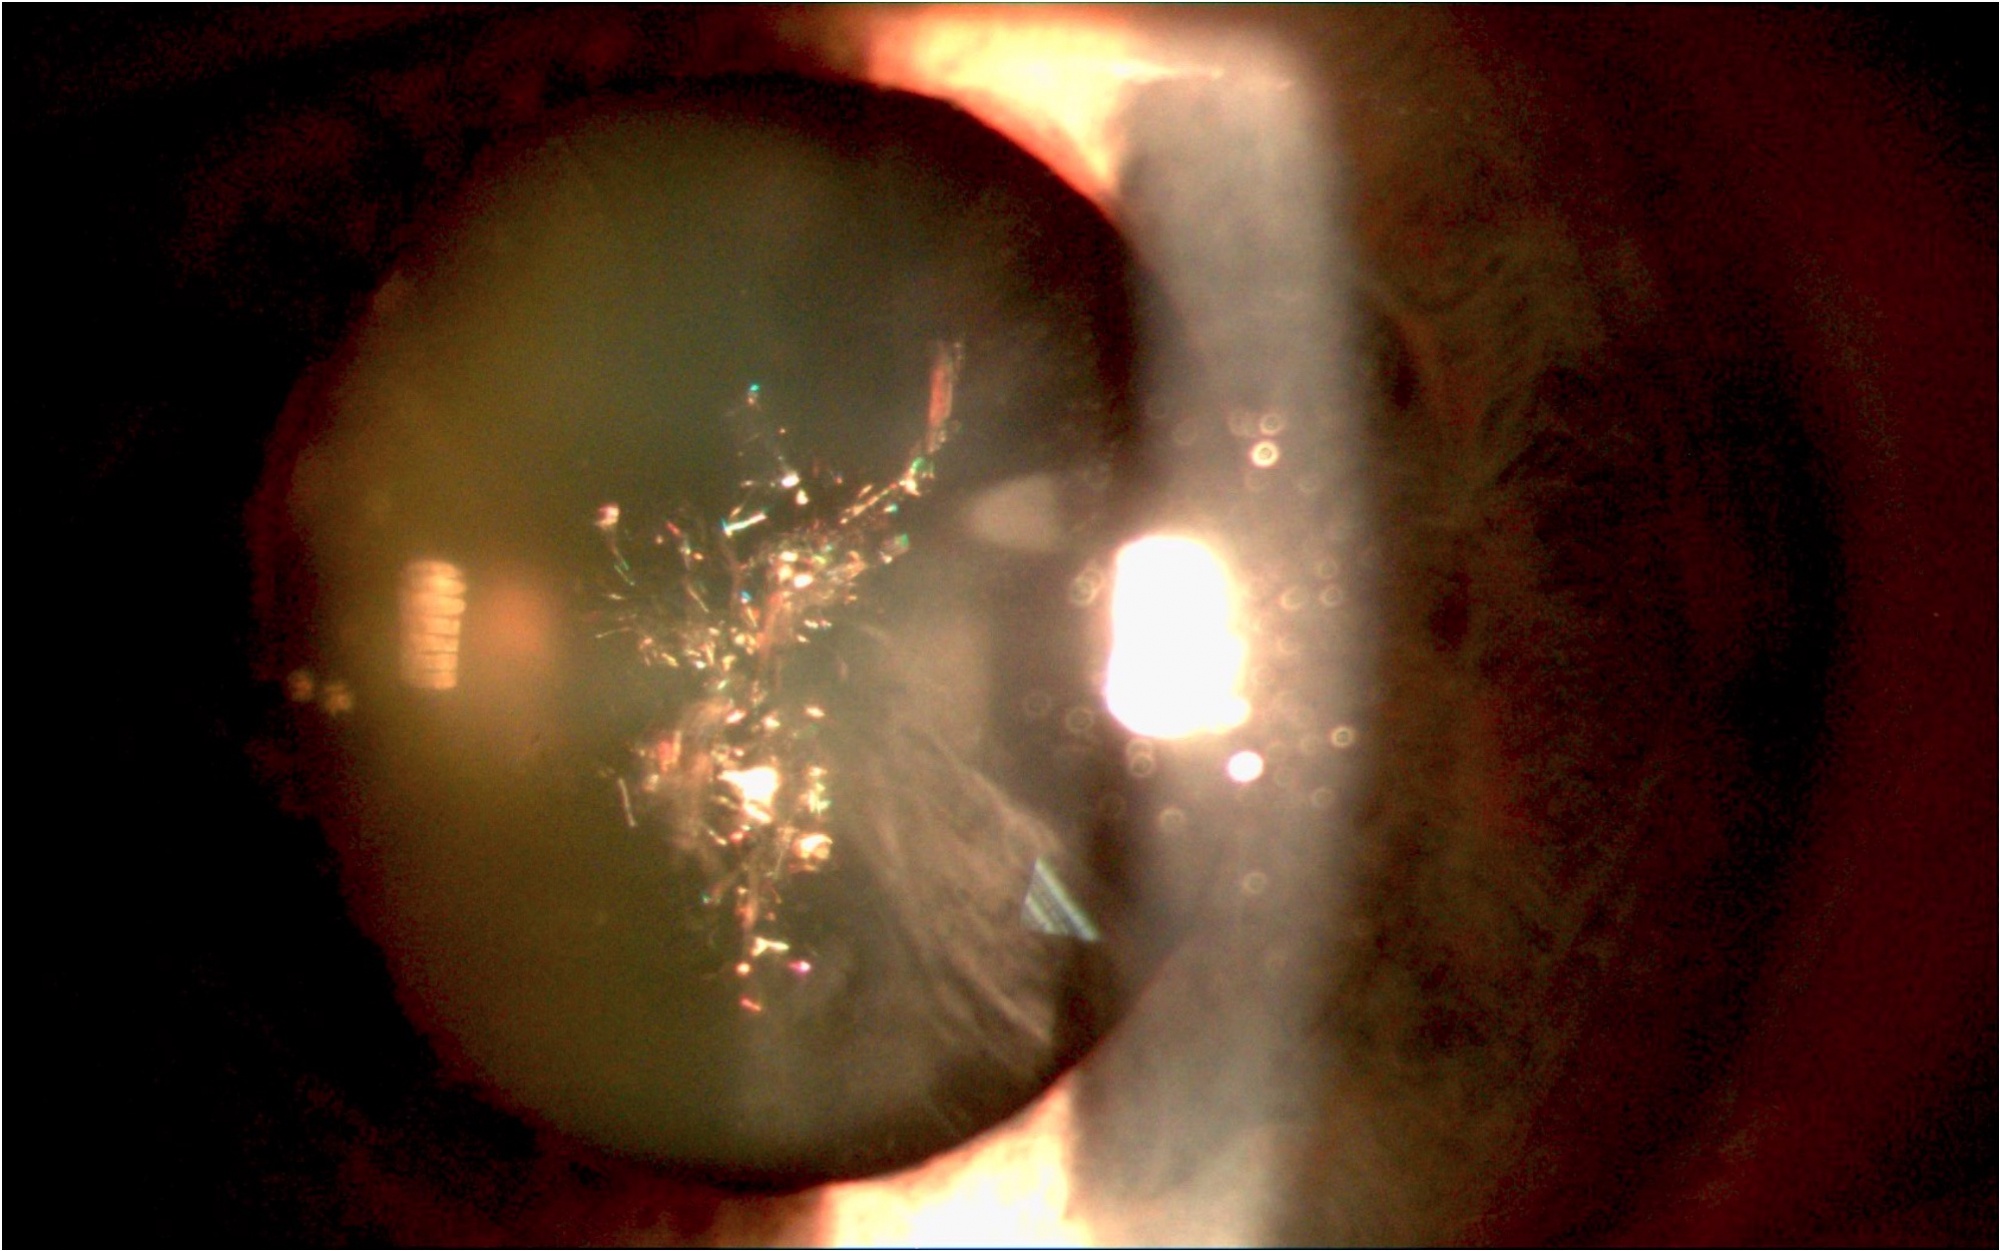

Sivý zákal – príčinou tohto ochorenia oka, nazývaného aj katarakta, je starnutie šošovky. Vyskytuje sa u ľudí približne od veku 60 rokov, v posledných rokoch často aj u mladších. Zákal je spôsobený obvykle zahusťovaním materiálu šošovky, ktoré je spôsobené rastom šošovkových vlákien vo vnútri šošovky. Pretože puzdro šošovky jej nedovoľuje rást do šírky a hrúbky ( do hrúbky šošovka napriek tomu trochu rastie) šošovka rastie do tvrdosti.

S postupujúcim kalením sa strácajú vo videní detaily a menej výrazné sú aj farby, klesá kontrast. Zakalenie šošovky bráni priechodu svetelných lúčov na sietnicu. Časom sa zakalenie stupňuje a videnie sa zhoršuje. Sivý zákal môže spôsobiť aj slepotu. Riešením je iba operácia (ktorá trvá približne desať minút), pri ktorom sa zakalená šošovka nahradí umelou ktorá je číra.

Sivý zákal typu „christmas tree“. Pripomína rozsvietený vianočný stromček. Vyskytuje sa vzácne. Zhoršuje videnie, preto je potrebná operácia.